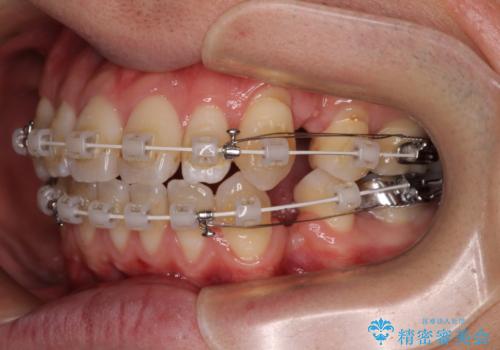

- 矯正装置

- 審美装置

装置は、透明感のあるクリアブラケットとホワイトコーティングされたワイヤーを使用した、目立ちにくい審美装置を選択。

周囲に気づかれにくく、日常生活にも自然に溶け込みます。